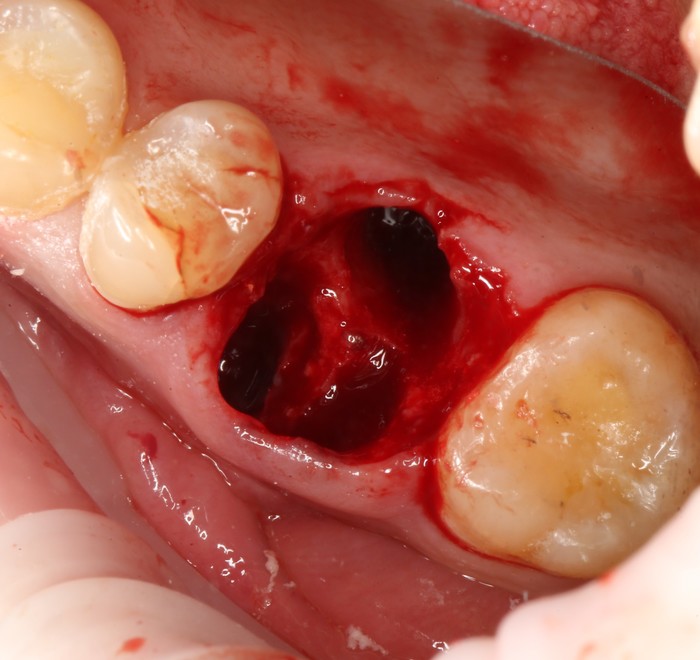

Установлена заглушка, которая закрывает шахту имплантата.

Теперь необходимо выждать около 2-х месяцев для того, чтобы десна восстановилась (Пациентка это время ходила со специальной капой, которая имитирует наличие зуба).

Далее проведена пластика десны, снова два месяца ожиданий и установка временной коронки: